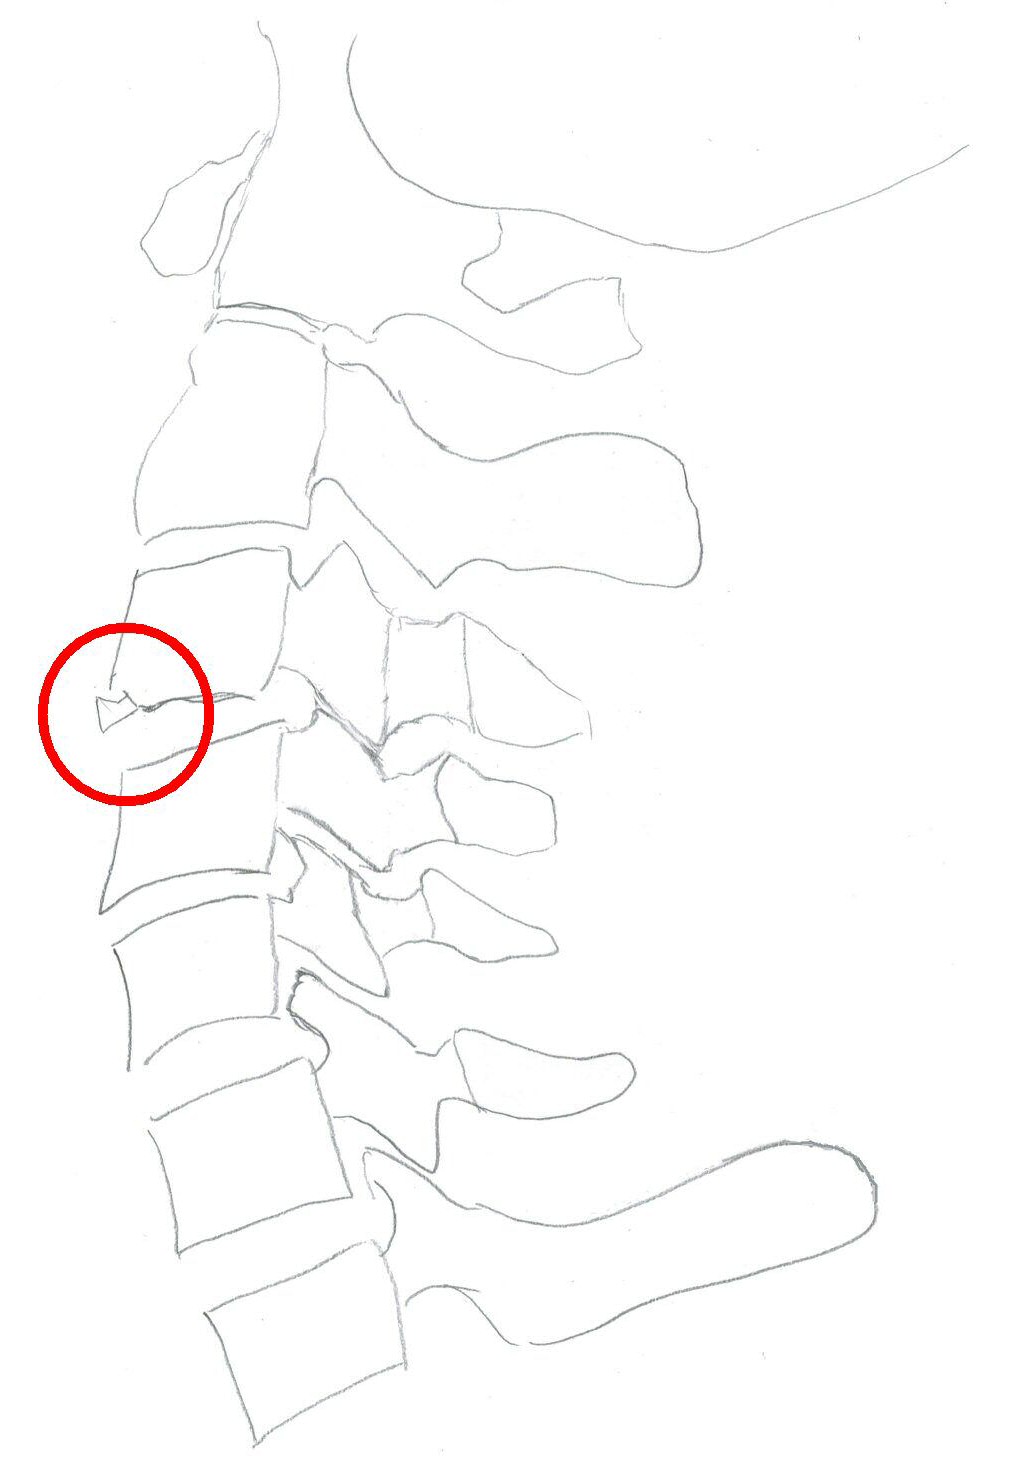

Teardropfrakturer

Typiskt äldre patient med degenererad halsrygg som fallit på pannan berusad. DT med diskreta fynd, kan vara helt normal, visa extensions teardrop (se bilder nedan) eller distraktion i disk. Kan vara mycket instabil.